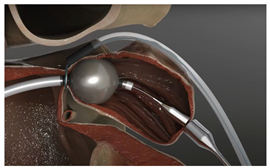

(Photo courtesy Biosense Webster) | Laminar LAAX System [93] Biosense Webster, Inc. | Rotational closure mechanism with integrated ball and lock design; self-expanding nitinol ball structure for LAA tissue engagement; no hooks or barbs required for anchoring, minimal LA-facing surface area; 18-F double-curve steerable guide system; two device sizes (12 mm and 16 mm). | Long-term durability data still being collected; currently in pivotal trial phase; learning curve for novel rotational closure technique; limited real-world experience outside clinical trials; optimal patient selection criteria still being established. |